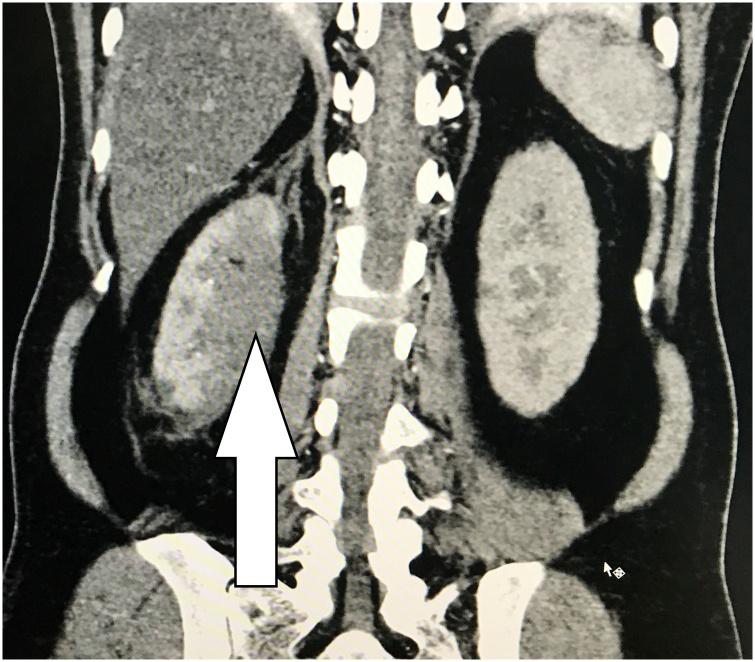

Rare renal embolic manifestation of left atrial myxoma: A case report.

Aspiration Thrombectomy of Acute Atrial Fibrillation-related Renal Artery Thromboembolism in a Patient with Horseshoe Kidney.

Acute renal infarction: a single center experience.

Clinical Characteristics and Outcomes of Renal Infarction.

Acute renal infarction: a case series.

Acute renal embolism. Forty-four cases of renal infarction in patients with atrial fibrillation.